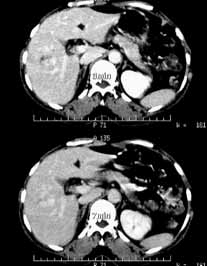

肝血管瘤06

女性,55岁,右上腹间有隐痛不适半年余。

ct诊断:肝右前叶下段血管瘤。